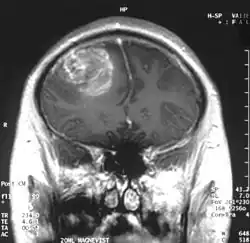

A coronal view (from the back of the head) of a contrast-enhanced MRI revealing a glioblastoma in a 15-year-old boy | |